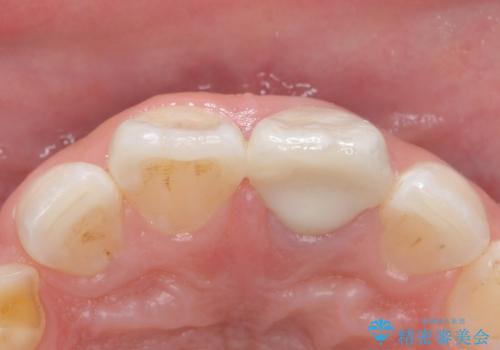

歯の黒ずみを完全に見えなくすることができ、大変喜んでいただけました。

被せ物を装着する際は、歯の中(根管)から綺麗にすることも重要となります。